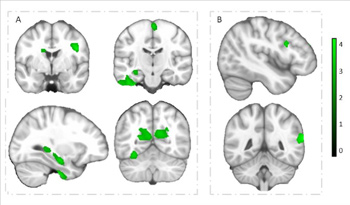

Regiones cerebrales que muestran asociaciones independientes positivas de velocidad cardiorrespiratoria y agilidad de velocidad con volumen de materia gris en niños con sobrepeso u obesidad. /UGR

En particular, la capacidad aeróbica se asoció con mayor volumen de materia gris en regiones frontales (corteza premotora y corteza motora suplementaria), subcorticales (hipocampo y caudado), regiones temporales (giro temporal inferior y giro parahipocampal) y la corteza calcarina; regiones cerebrales importantes para el aprendizaje, la función ejecutiva y procesos motores y visuales.

A su vez, en la investigación liderada por la UGR, la habilidad motora se asoció con mayor volumen de materia gris en dos regiones claves para el procesamiento del lenguaje y la lectura, el giro frontal inferior y el giro temporal superior. Sin embargo, la fuerza muscular no mostró ninguna asociación independiente con el volumen de materia gris en ninguna región del cerebro.